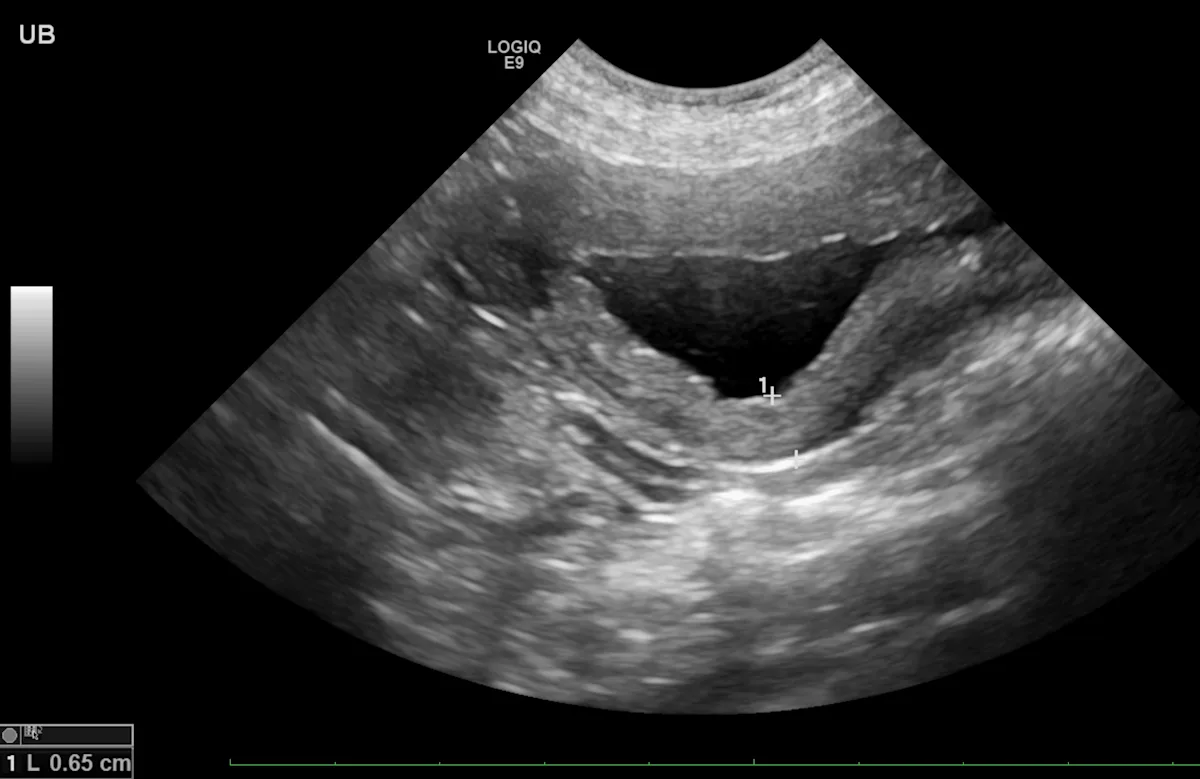

Patients with chronic polypoid cystitis (Figure 2) can also have multiple projections of soft tissue into the lumen of the urinary bladder. Identification of these protrusions and histopathology, in addition to clinical signs of recurrent UTI or results of traumatic catheterization, are needed to differentiate polypoid cystitis and neoplasia.

Sagittal image of the urinary bladder with soft tissue extending into the lumen, indicating a presumed polyp in a 12-year-old spayed bichon frise crossbreed. Color flow Doppler shows the single vessel extending into the lesion. Left, cranial; bottom, dorsal